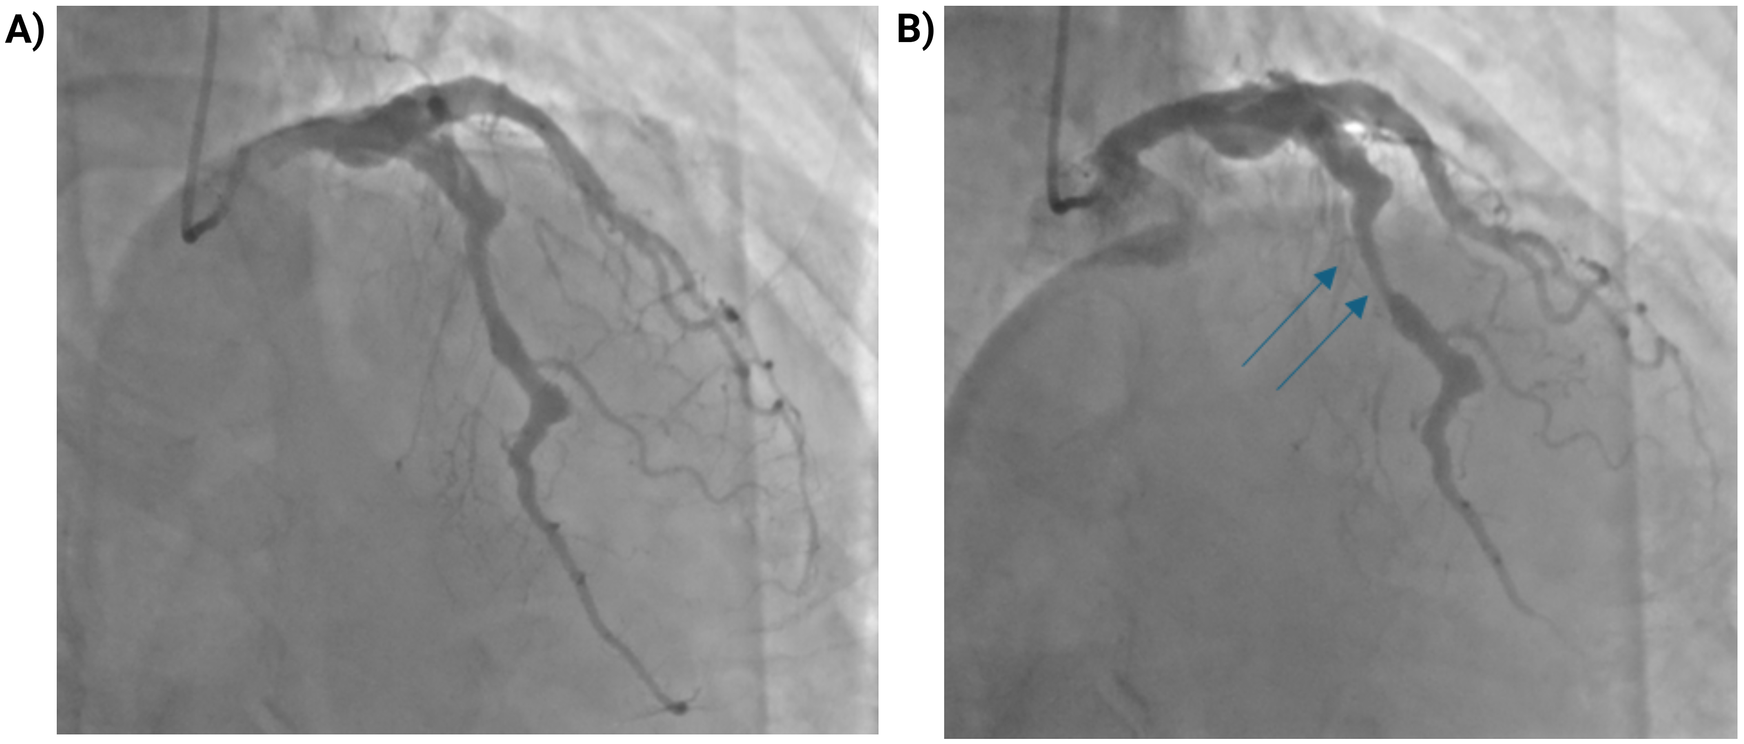

Coronary angiography demonstrated diffuse coronary ectasia involving all major epicardial vessels (Markis type I) with slow TIMI 2 flow. Maximal reference diameters exceeded 8.7 mm in the right coronary artery, 7.2 mm in the circumflex, and 7.1 mm in the left anterior descending (LAD) artery (Figure 1). The mid-LAD showed a prominent myocardial bridge (MB) with a characteristic “milking effect” (∼75% systolic compression), likely accentuated by the surrounding ectatic reference segment (Figure 2). The intermediate branch displayed a severe ostial lesion followed by aneurysmal dilatation (maximum diameter 6.5 mm) and was deemed unsuitable for PCI. Diffuse, non-obstructive atherosclerotic plaques were present throughout the coronary tree without significant fixed stenoseS.

Figure 2

Myocardial bridging of the mid-LAD with dynamic systolic compression. (A) Coronary angiogram in diastole showing the mid-LAD segment. (B) During systole, dynamic compression of a myocardial bridge in the mid-LAD segment (blue arrows) produces a “milking effect” with approximately 75% systolic narrowing. The apparent degree of stenosis may be overestimated due to the surrounding coronary ectasia.